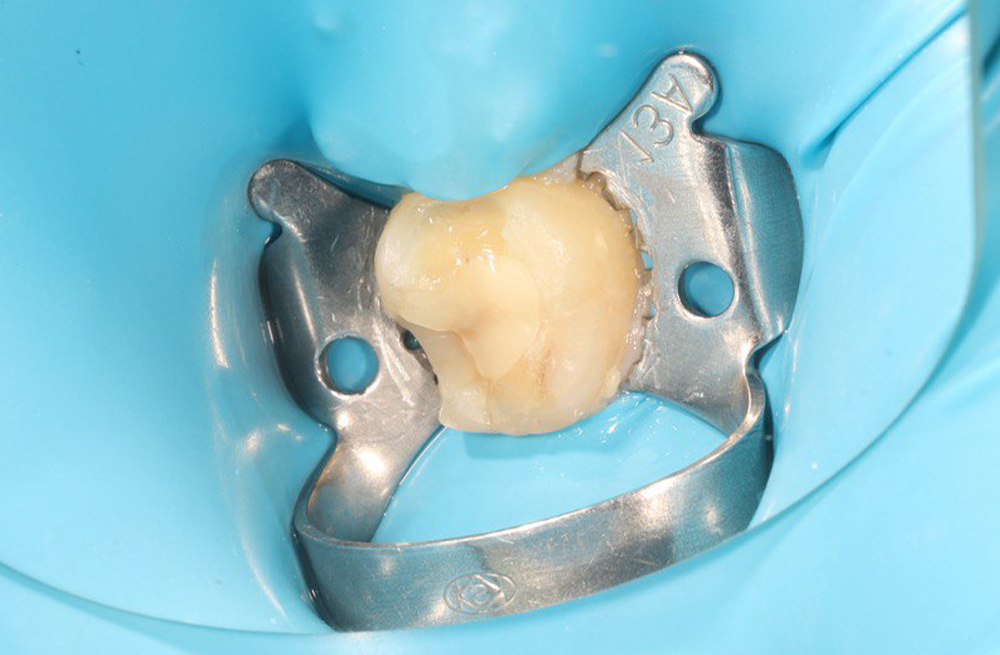

Препарирование и реставрация 36 зуба при вторичном кариесе с надежной изоляцией и полировкой пломбы